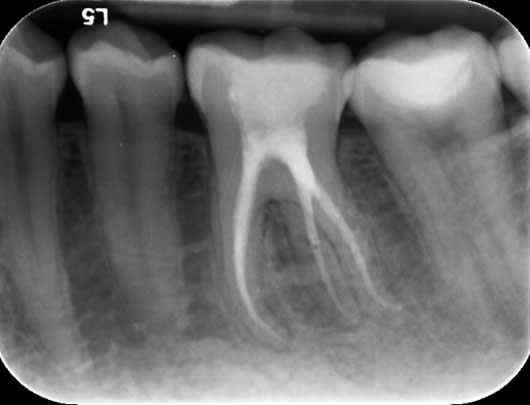

Case 1: Root canal treatment – long roots.

This patient presented with a history of a dull pain and swelling from his upper left second molar (UL7). The tooth had a crown and was tender when tapped. A radiograph (X-ray photograph) showed that there was a large shadow around the roots. This shadow indicates bone loss caused by infection within the root canals. The diagnosis for this tooth was ‘Chronic apical periodontitis’; and the treatment options were either extraction or root canal treatment. After discussion with the patient, we decided to proceed with root canal treatment. As the crown was in good condition, we decided to keep it in place and access through the top of it. This way, a new crown would not be needed after our treatment. In this tooth, all the canals were found; they were long but after careful progress we were able to negotiate to the ends of the roots. This is important as it means we can take our disinfectant solutions to the full length of the canals, enhancing our cleaning potential. The canals were prepared (enlarged to improve penetration of the cleaning solutions), cleaned and filled. A radiograph taken after one year shows good healing as the ‘shadow’ has gone due to regeneration of bone.

Before treatment UL7 - note the ‘shadowing’ around the roots.

Following root canal treatment - the ‘white lines’ are the root fillings within the root canals.

One year review – note the healing of the previous ‘shadow’.